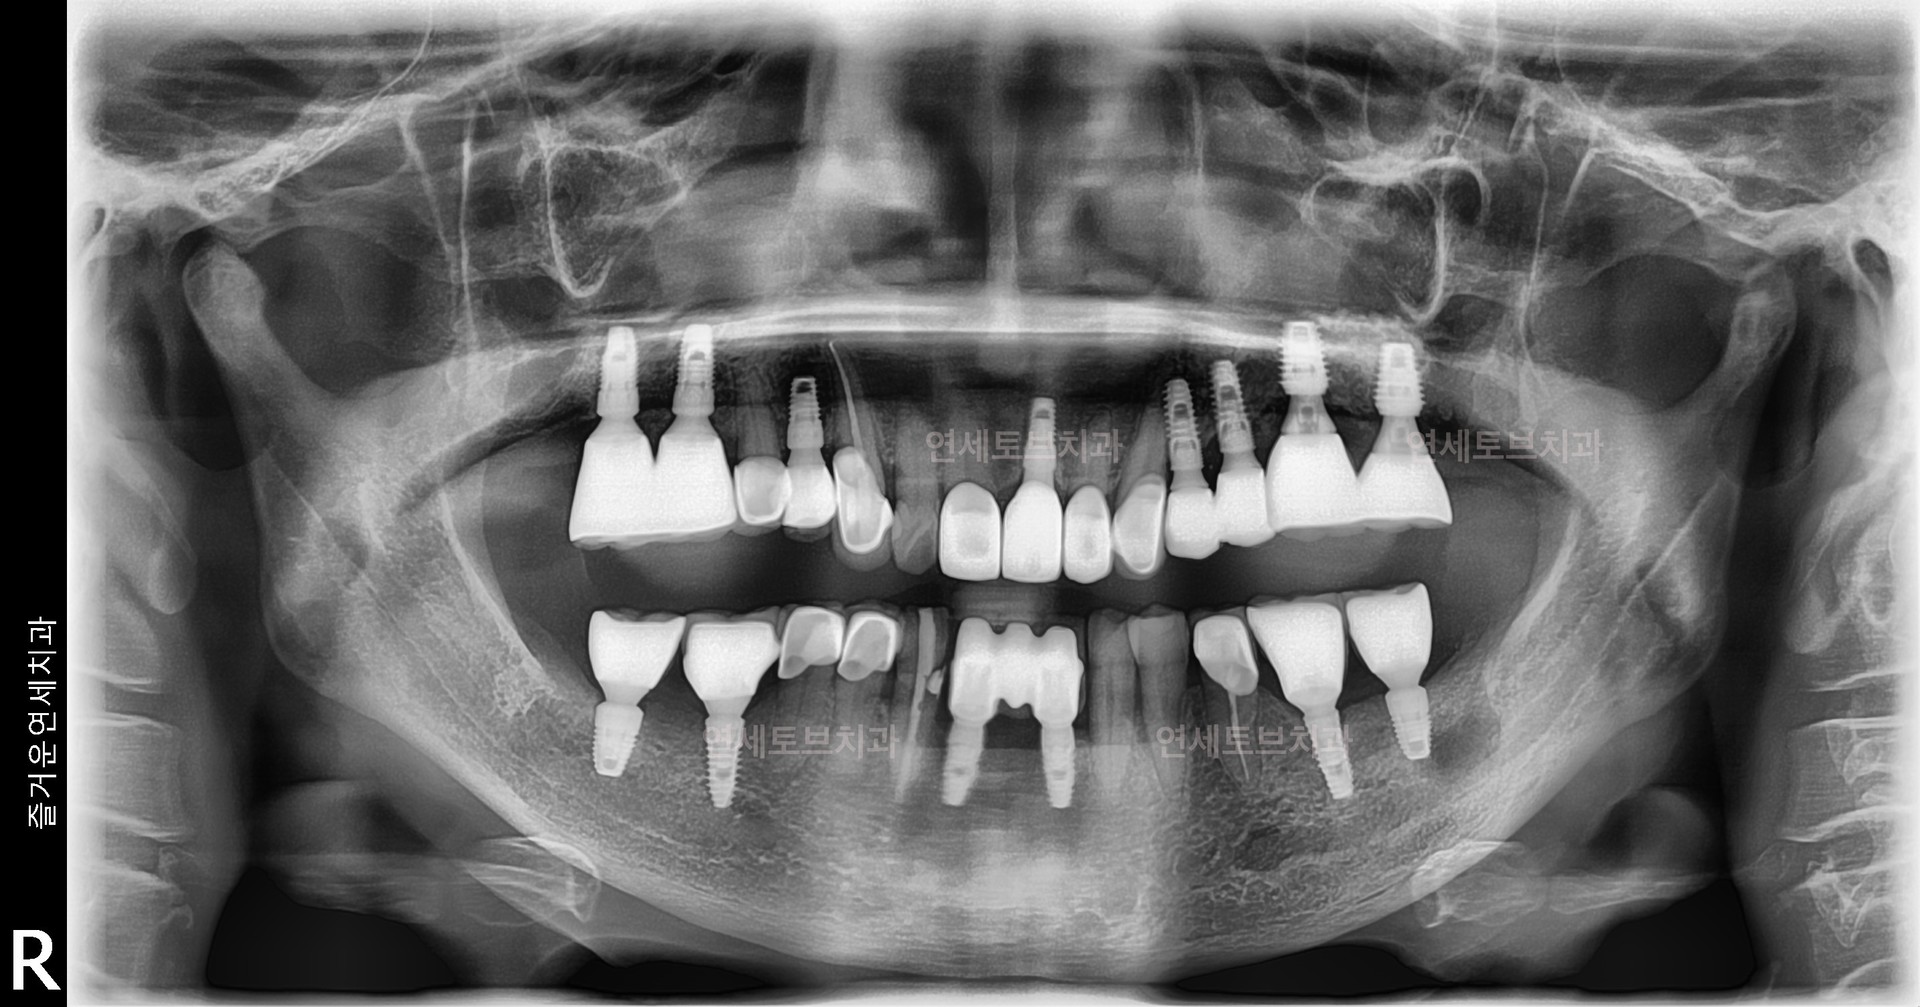

#1

#2

#3

#4